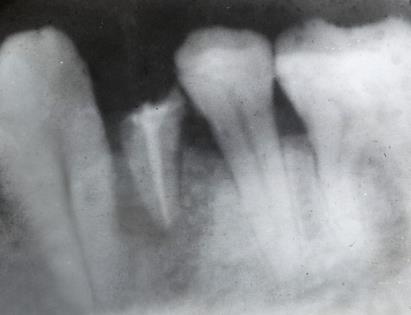

口腔殘根在拍攝X線片後發現牙根長度和粗度都不好,不能繼續使用的情況下,建議拔除後鑲牙,如果執意不拔的話,會(hui) 出現很大的危害: